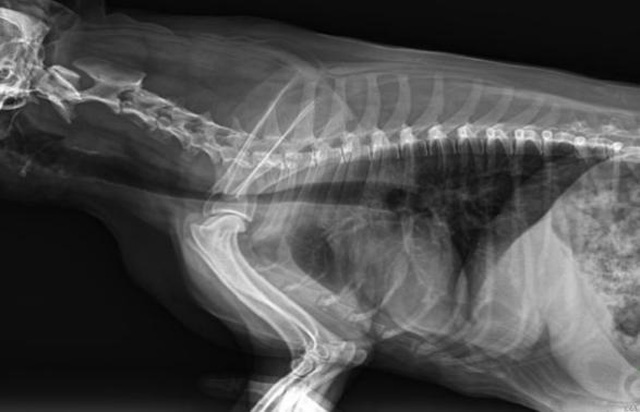

從臨床角度出發(fā),大力發(fā)展動態(tài)DR,以精準的診斷為小動物保駕護航。寵物DR升級使用雙焦點球管,大尺寸平板探測器,超高頻逆變高壓發(fā)生器。醫(yī)用纖維板臺面,防止寵物劃傷。寵物DR整機小巧實用,骨略結(jié)構(gòu)和器官位置,分類詳細,運算更快,讓拍攝條件更科學,有助于提高診斷的準確性和效率。安裝移動非常方便。低輸入電流設(shè)計,220伏常規(guī)電壓。多品種動物程序設(shè)定,滿足各個臨床需求。成像效果顯著,寵物不能言語表達,導致誤診率居高不下。寵物診療均以經(jīng)驗診斷為主的方式,確保最小化輻射降低對醫(yī)生及動物的影響。以滿足精細化的寵物醫(yī)療需求,成為診斷寵物內(nèi)外科疾病的必備工具。使醫(yī)院更有競爭力,為醫(yī)院創(chuàng)收增光添彩。

寵物DR的操作流程是什么呢?第一步首先插上整機電源,然后按下主機電源。打開高壓發(fā)生器的電源,工作站主機電源。等待主機軟件的自動啟動。通過軟件登記檢查的寵物信息,選擇寵物檢查拍攝部位。調(diào)節(jié)限速器拍攝區(qū)域。關(guān)閉鉛房門,點擊開始拍攝按鈕。拍攝完成調(diào)整圖像并且輸出。